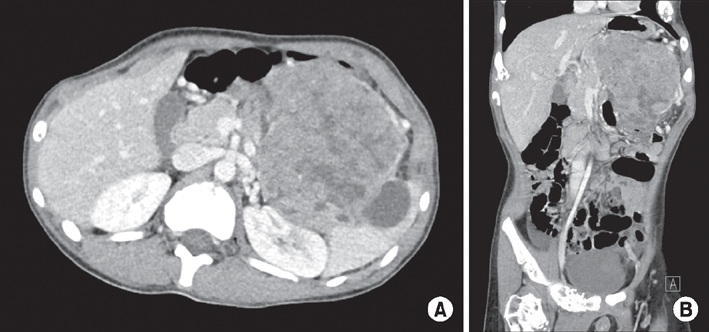

A 9.8×10.0-cm mass of uncertain origin was detected close to the pancreas and spleen on abdominal ultrasonography and abdominal-pelvic CT. The mass was lobulated and heterogeneously enhanced with a multifocal cystic portion around the spleen (

Fig. 1). Fine needle aspiration biopsy (FNAB) was planned and conducted to determine the possibility of neuroendocrine tumor and pancreatoblastoma. However, we could not make a definitive diagnosis; pancreatoblastoma was suspected based on the presence of beta-catenin positive cells. There were no remarkable findings on a preoperative chest CT or a bone scan to detect metastasis.

Fig. 1(A, B) Abdominal-pelvis CT showing a 9.8×10.0-cm, heterogeneous, enhancing, solid, cystic mass in the left upper quadrant.